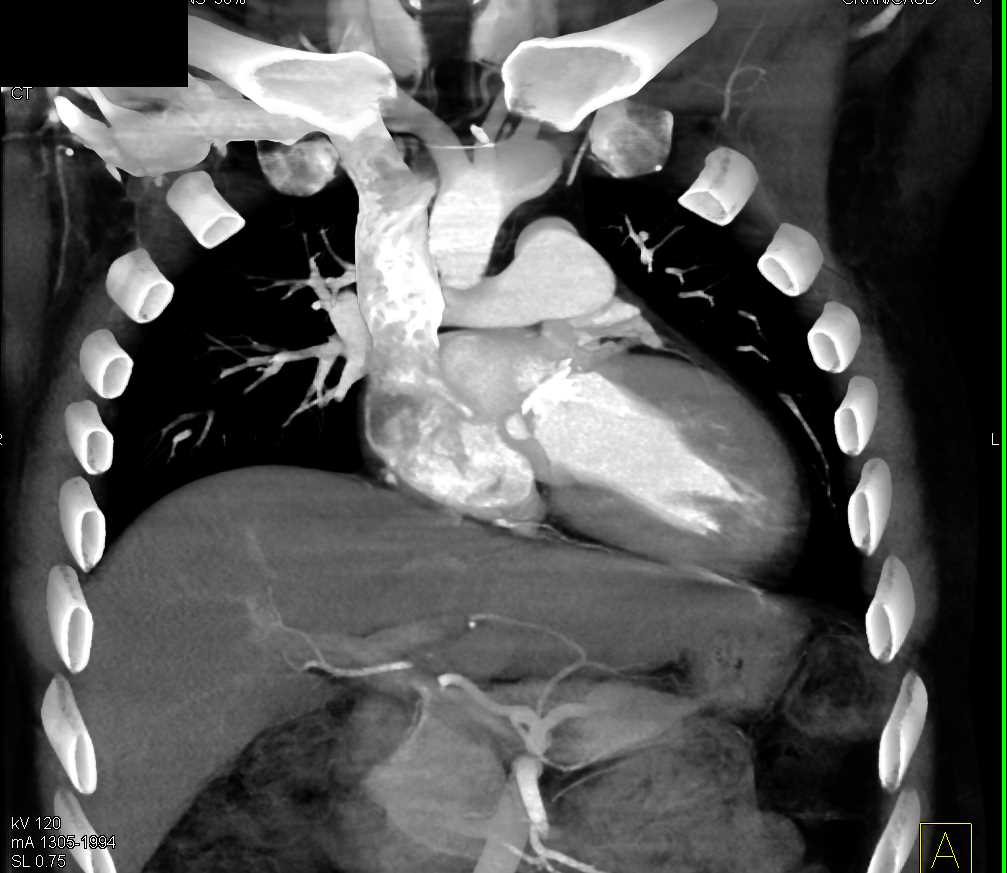

Aortic Valve Repair